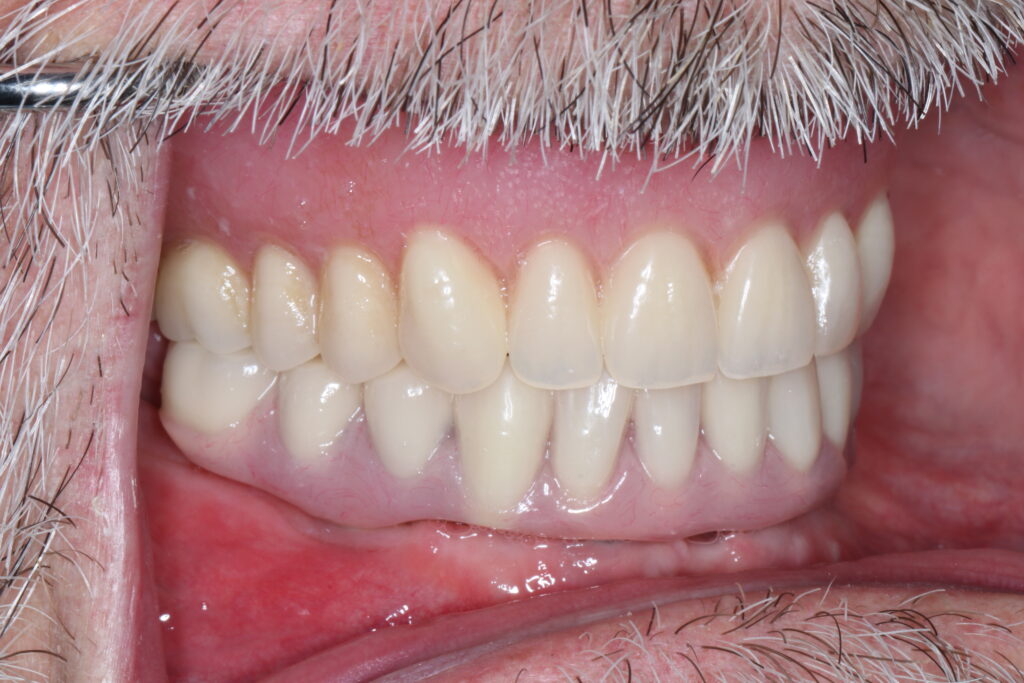

A selection of full arch fixed implant bridge patients after 5 years of wear

Oral Surgeons – Dr Han Choi, Dr Sam Goldsmith, Dr Rajiv Rajpal NSOMS

Prosthodontist – Dr Alan Payne NSOMS/Northland Prosthodontics

Dental technicians – Hosaka Takashi, DT Denture Design, Auckland, CJ Park, Project Dentistry, Auckland and Osteon Medical, Melbourne, Australia.